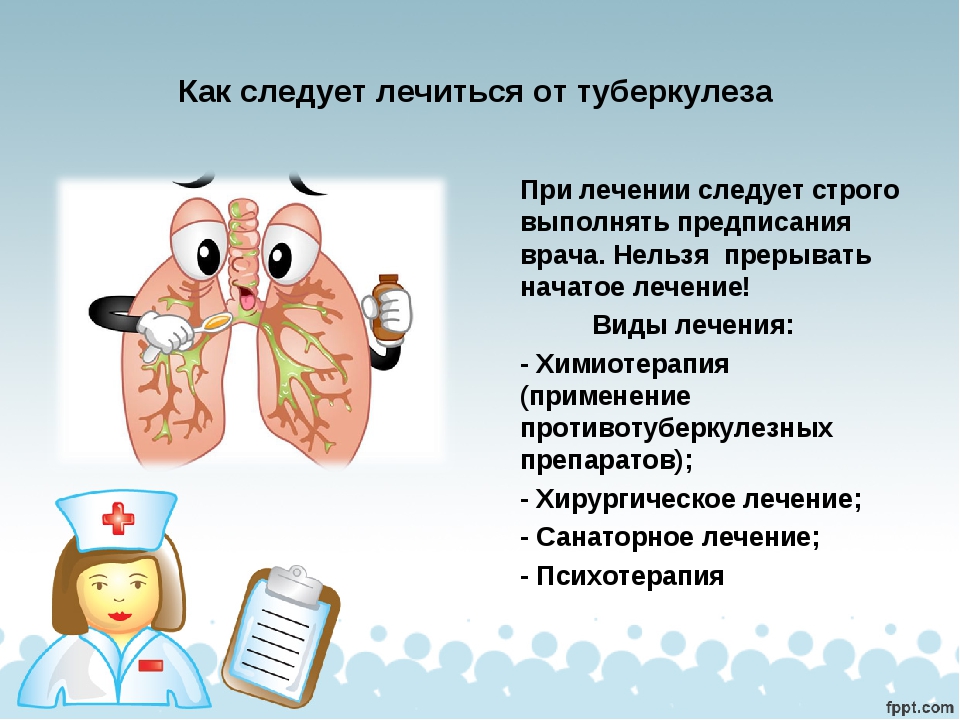

Современные методы лечения туберкулеза